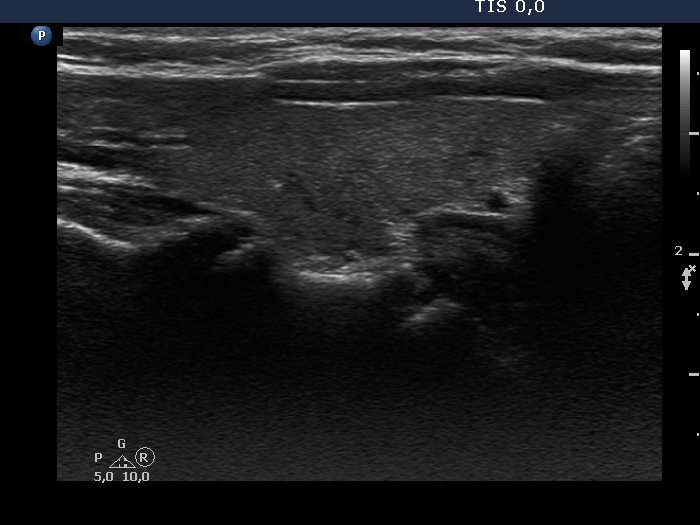

The echogenicity of the nodule - case 2071 (ultrasonographic picture 5)

Left lobe, longitudinal scan.